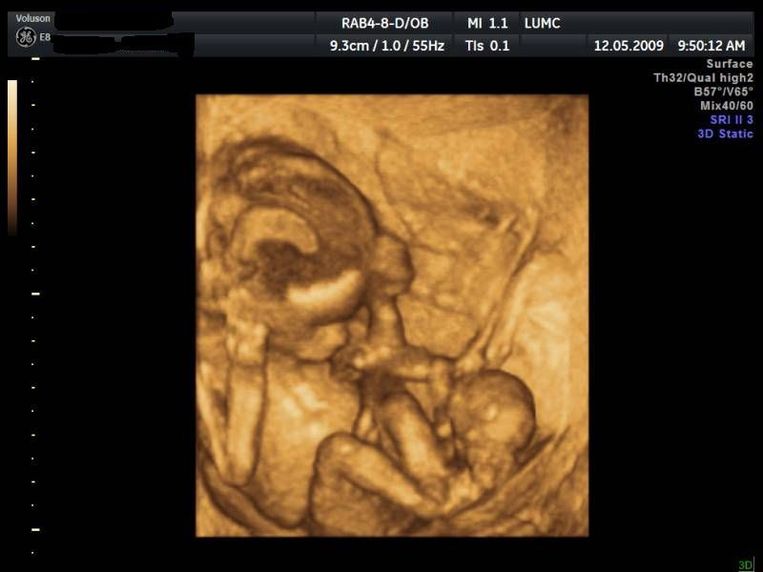

Rond de 32 tot 34 weken bespreekt de gynaecoloog de bevalling met je. Vanaf de eerste echos op 7-8-9 weken was er een duidelijk verschil in grootte tussen onze tweeling. Met een GUO wordt alles van top tot teen gecheckt bij je baby van de aderen in de hersenen tot elke hartkamer apart. Je ziet de babys dan bewegen en je kunt zelfs kijken of ze jouw neus hebben of toch echt die van hun papa Een 3D echo laten maken van je tweeling kan natuurlijk bij pretechozo. Als je een meisje krijgt heeft ze al 2 miljoen eicellen in haar eierstokken. Duwde ik links kreeg ik een schopje duwde ik gelijk daarna aan de andere kant kreeg ik ook weer een schopje.

Dan is duidelijk hoe de babys liggen. Een tweeling is vaak een verrassing en brengt naast blijdschap ook veel vragen met zich mee. Uitgebreide informatie over de 20 weken echo is te lezen in de landelijke brochure van het RIVM. Bij een zorgvuldig uitgevoerde echo is het bijna niet mogelijk om een tweeling te missen. Ook is het tegenwoordig mogelijk om een 3D echo te laten maken. Duwde ik links kreeg ik een schopje duwde ik gelijk daarna aan de andere kant kreeg ik ook weer een schopje.